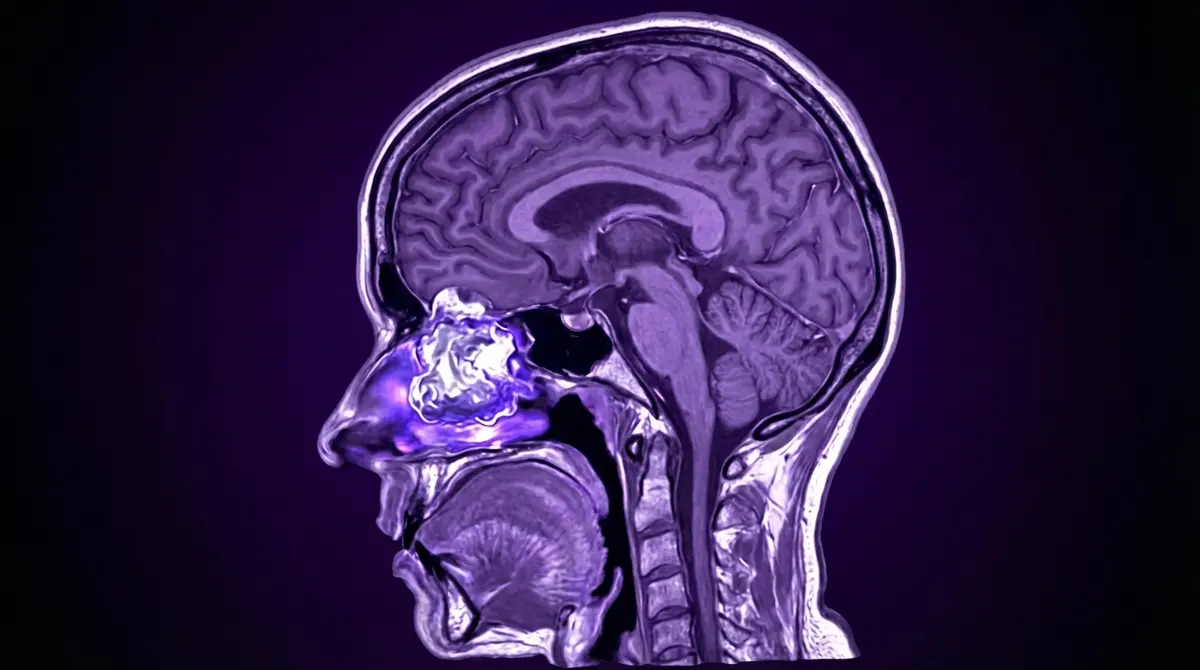

Tumor raro que nasce da mucosa olfativa (tecido de cheiro no topo da cavidade nasal). Apesar de "neuroblastoma" no nome, é diferente do tumor infantil comum. Afeta adultos. Cresce para cima, entrando na fossa craniana anterior, comprimindo o cérebro frontal.

- 🧠 RM da base do crânio (ver extensão intracraniana)